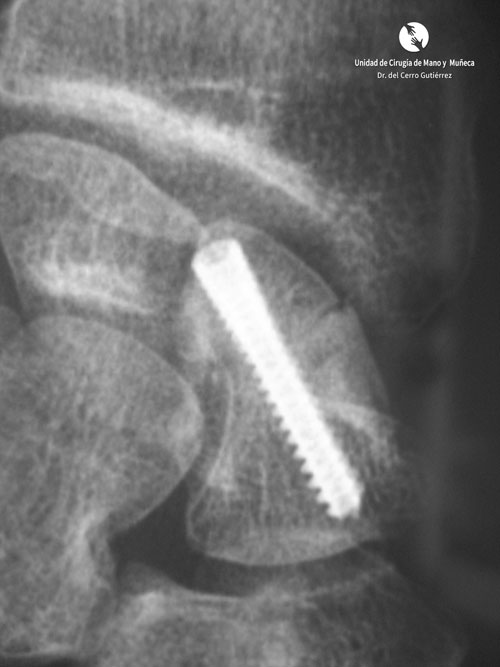

Fractura del Escafoides Pseudoartrosis escafoides injerto con tornillo

Pseudoartrosis escafoides injerto con tornillo

Fractura del Escafoides Tornillo con Injerto